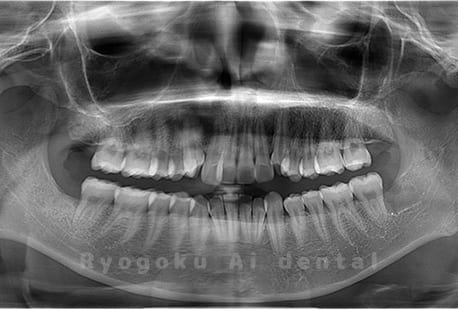

Case02

- 原因

- 下顎の水平埋伏智歯

- 治療内容

- 下顎の水平埋伏智歯を抜歯

<リスク・副作用>

手術後は痛み、腫れ、痺れなどの副作用が生じる場合があります。